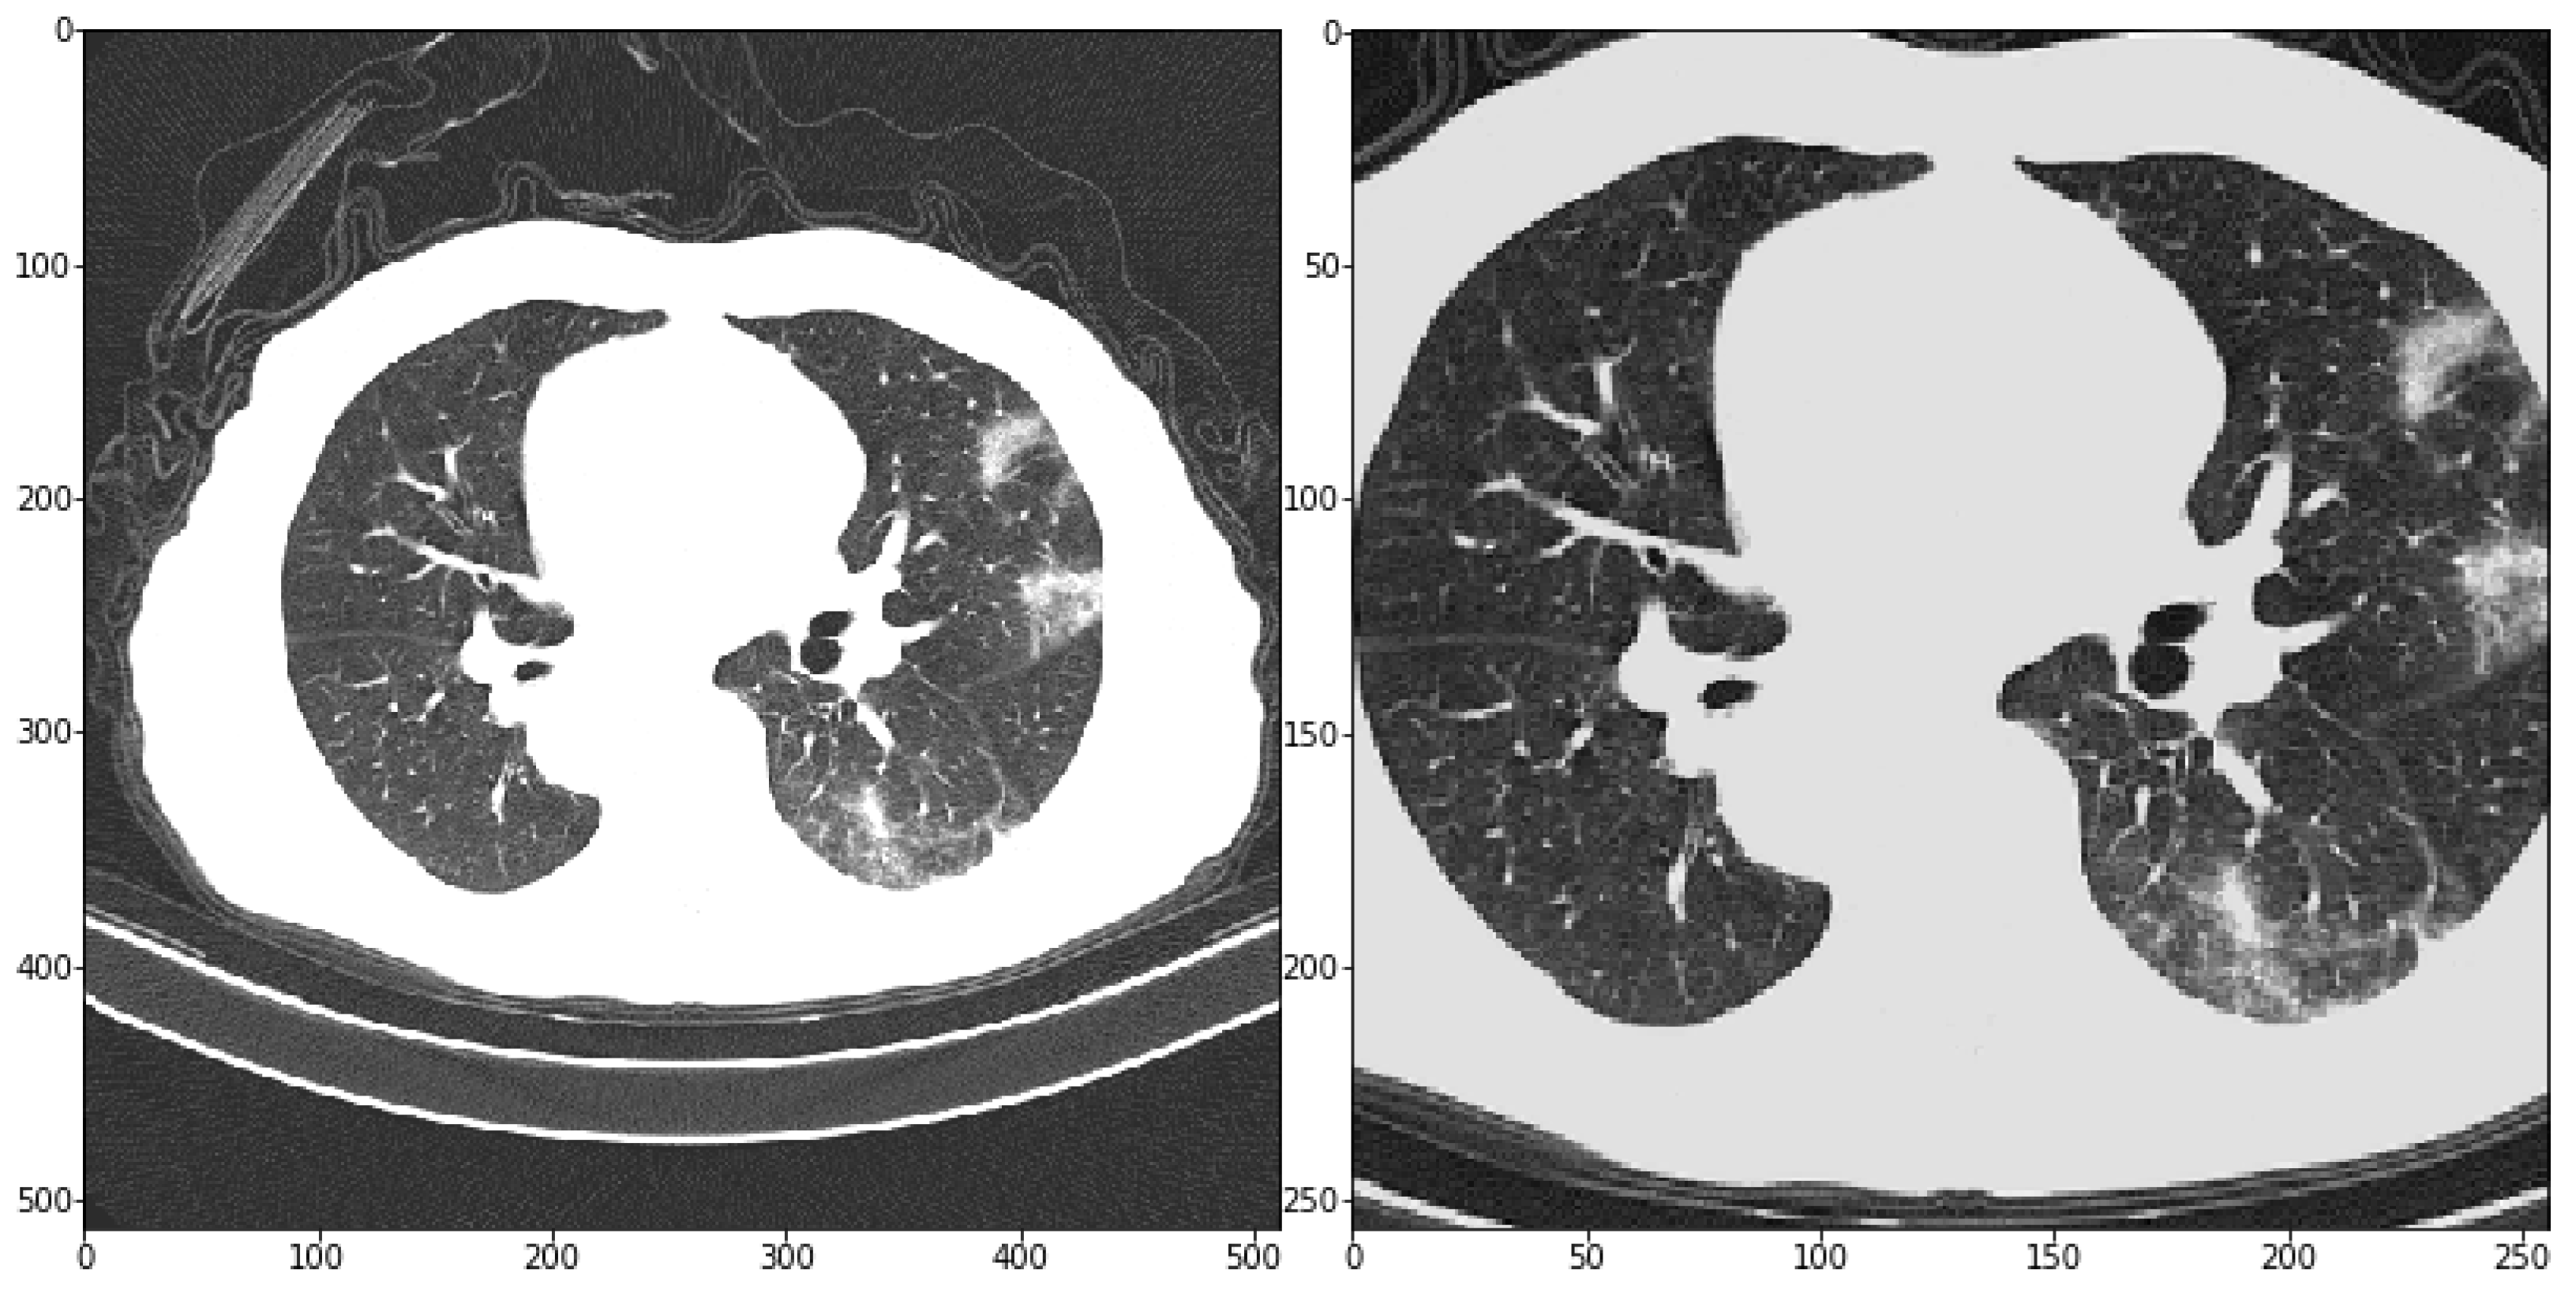

In addition, the size of the slices had to be reduced to meet the memory constraints of the GPU. To this end, the central part of each slice has been cropped with a fixed size and then scaled to 256 × 256 pixels (see Figure 6). The cropping has been aimed at removing contents non-informative for the problem at hand but that might affect the training phase.

Figure 6.

The left side shows an original chest CT slice of size 512 × 512. The right side shows the same chest CT slice after the pre-processing. The slice has been cropped in the center and then scaled to 256 × 256 pixels.